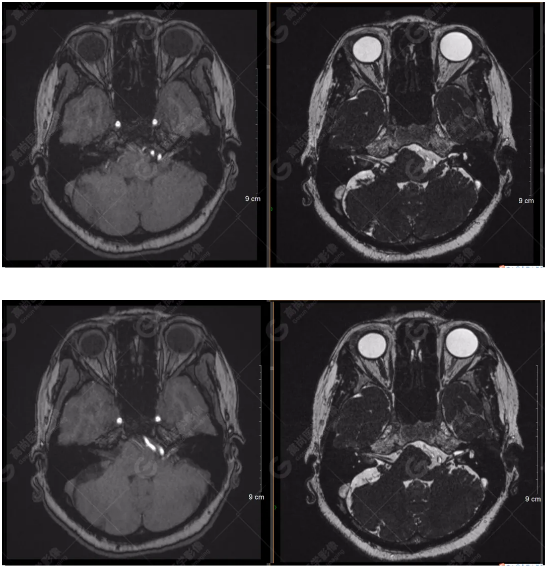

檢查圖像

顱腦MRA及ciss序列示腦基底動(dòng)脈環(huán)完整,雙側(cè)頸內(nèi)動(dòng)脈末段、大腦前動(dòng)脈、大腦中動(dòng)脈、大腦后動(dòng)脈及其主要分支顯影良好,管徑及走行正常,無明顯局灶性增粗或變細(xì)。雙側(cè)椎動(dòng)脈末段沿延髓左側(cè)向上走行,左側(cè)面聽神經(jīng)輕度受壓移位,左側(cè)面聽神經(jīng)周圍見細(xì)小血管包繞。右側(cè)面聽神經(jīng)及雙側(cè)三叉神經(jīng)周圍未見異常血管影。

1.雙側(cè)椎動(dòng)脈末段沿延髓左側(cè)向上走行,左側(cè)面聽神經(jīng)輕度受壓移位,左側(cè)面聽神經(jīng)周圍見細(xì)小血管包繞,可符合面聽神經(jīng)壓迫綜合征。